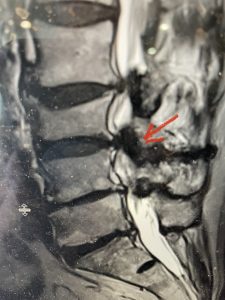

This 57 year-old male had a long history of low back pain and left lower extremity pain and numbness. The patient had failed conservative treatment of physical therapy and epidurals. MRI revealed tight left L2-3 and L3-4 lateral recess stenosis as well as significant right L4-5 facet arthropathy and right lateral recess stenosis as well as a grade 1 L4-5 spondylolisthesis

(Fig 2) Sagittal T2-weighted lumbar MRI demonstrating (arrow) tight lateral recess stenosis

It was felt that the patient should undergo surgical decompression and fusion at L4-5 given his spondylolisthesis. Post operatively he had an uneventful course and he had relief of his leg pain.